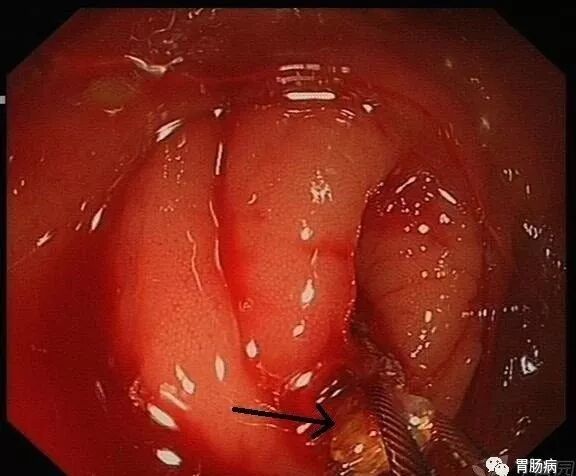

充分的肠道准备会有效减少ERAT操作时间,正常的阑尾开口部都被Gerlach’s瓣覆盖(如图,双箭头示Gerlach’s瓣);会造成插管困难,加上特制的锥形透明帽后插管就变得相对容易。

通过内镜前端的透明帽的帮助下,推开Gerlach’s瓣,并进行阑尾腔插管。

当黄斑马导丝及导管置入阑尾腔时,可见脓性分泌物涌出。